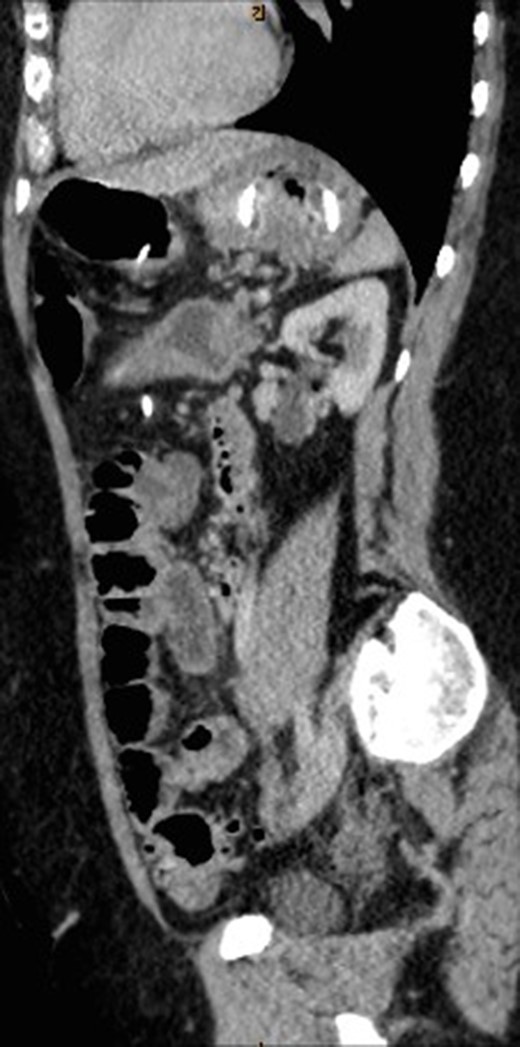

CT abdomen with oral and intravenous contrast was organized to further investigate the tubular foreign body. It revealed concurrent gastric band erosion into gastric lumen and connection tubing eroding into the posterior wall of transverse colon and exiting inferiorly (Figs 2–6). There was no evidence of any oral contrast leak from the stomach.

Sagittal view of CT abdomen showing the gastric band tubing eroding into posterior wall of transverse colon and exiting inferiorly.